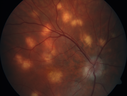

31 year old man with vision loss in the right eye more than the left eye. He has an anaplastic astrocytoma diagnosed 10/2017 the first one was 10/2014. These are different locations. They are treating them with Chemotherapy and Avastin. It might be that one might have spread from the other. He was clean for 3 years. He is on Avastin and Temozolomide but his blood counts have been good. December 2017 he had a herpes superficial infection in the right eye which responded to treatment. The last neurosurgery was October 2017. Going to Duke June 5 and seeing a neuroophthalmologist there. VA OD: Dcc20/40 PH20/25 NccJ5 VA OS: Dcc20/16 PH20/10 NccJ1+ His fundus is presumably nocardia, pneumocystis, aspergillis or cryptococcus. His LP was negative and he was tried on a course of antifungals. He was then lost to followup

Multifocal Choroiditis - Pneumocystis - aspergillis - cryptococcus671 views31 year old male with anaplastic astrocytoma on chemotherapy with mild vision loss in the right eye. LP did not reveal organism. He was placed on a trial of anti-fungal medications and lost to follow-up00000